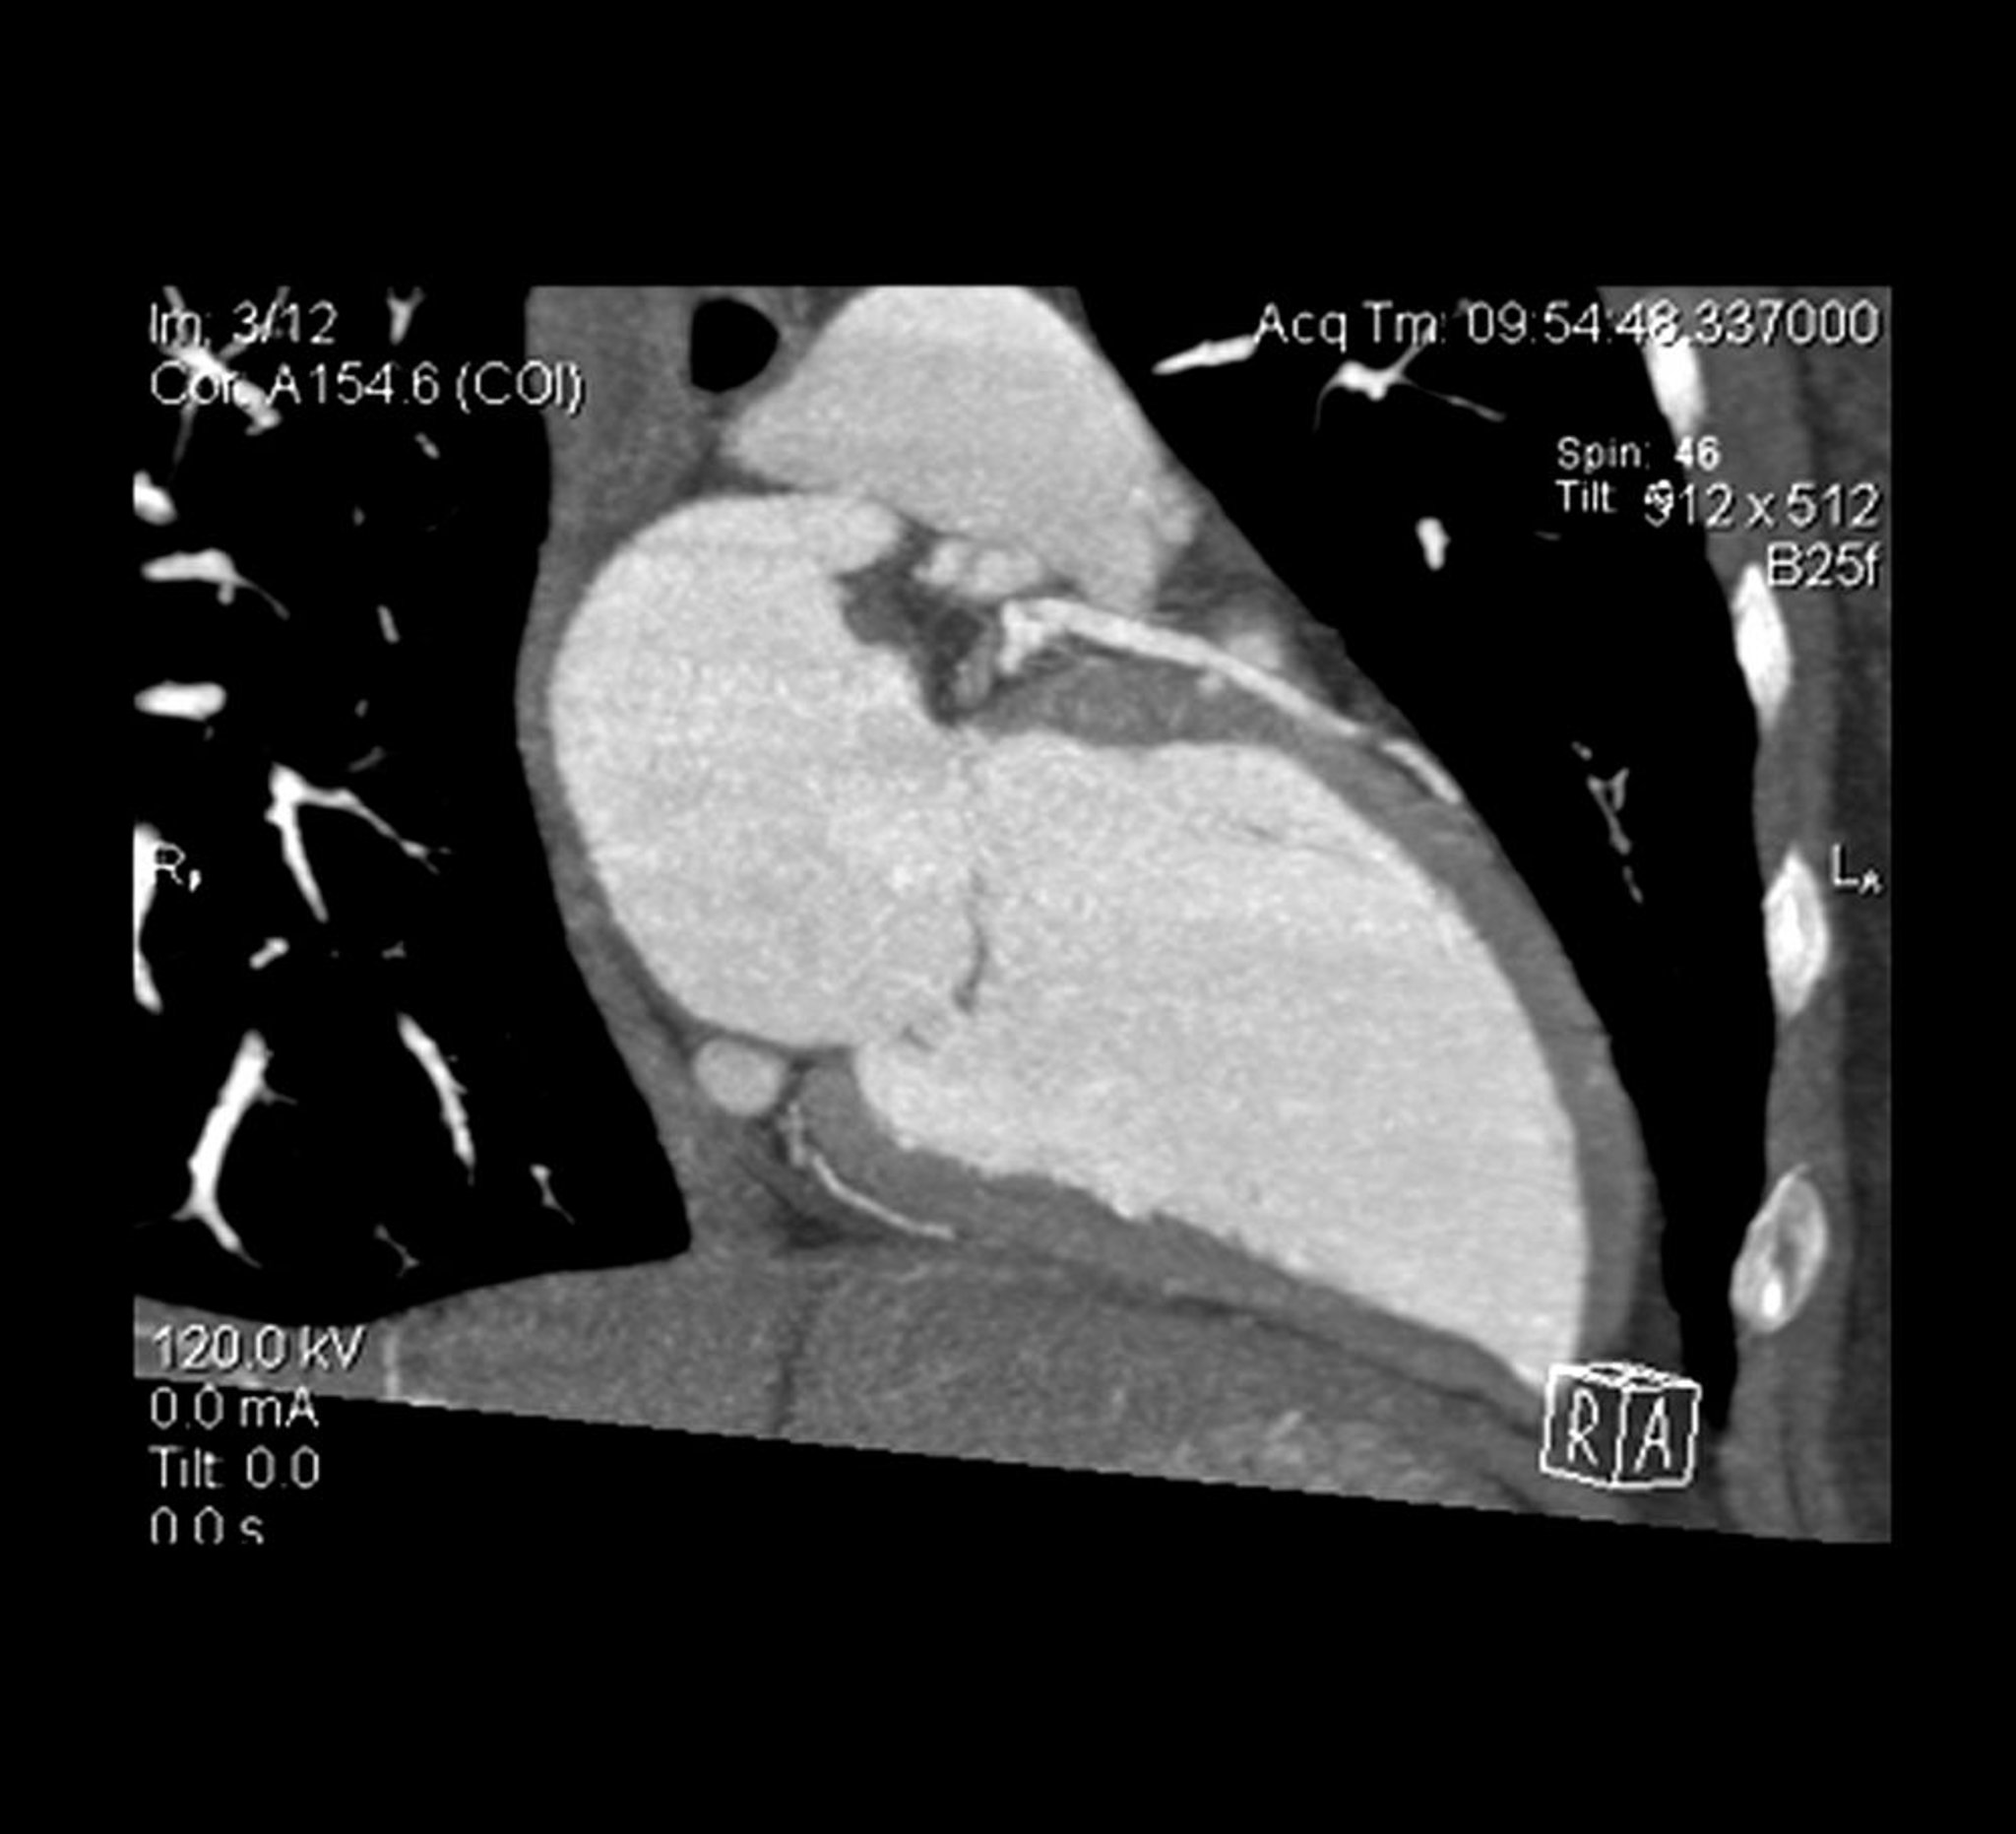

El corte transversal de un angiotomograma cardíaco muestra el ventrículo izquierdo y la arteria descendente anterior izquierda.